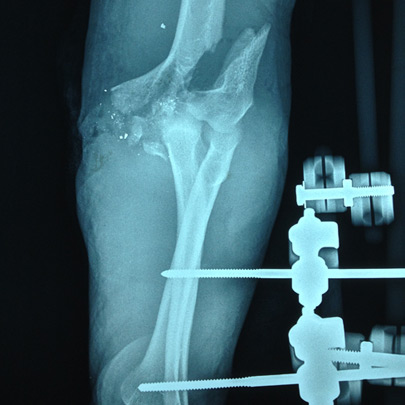

Fracturas y luxaciones

Lesiones complejas

Tratamientos quirúrgicos